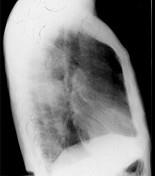

72岁,男,呼吸急促、气喘4个月,请结合胸片,选出最可能的诊断 ( )A.肺癌B.错构瘤C.肺结核D.韦格肉芽肿E.支气管腺瘤

问题 72岁,男,呼吸急促、气喘4个月,请结合胸片,选出最可能的诊断 ( )

选项 A.肺癌 B.错构瘤 C.肺结核 D.韦格肉芽肿 E.支气管腺瘤

答案 A